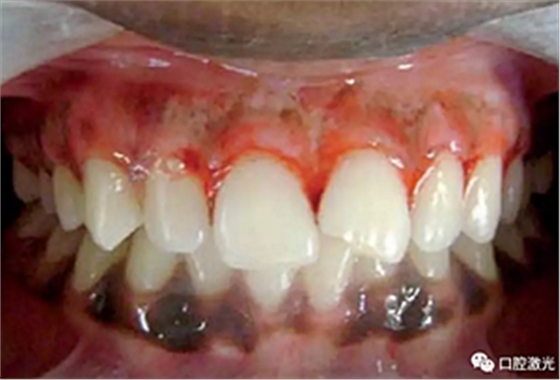

术后即刻

患者术后无明显疼痛不适,没有出现大量出血、感染或结痂现象。整个恢复过程较为顺利。患者接受度高,治疗效果明显。